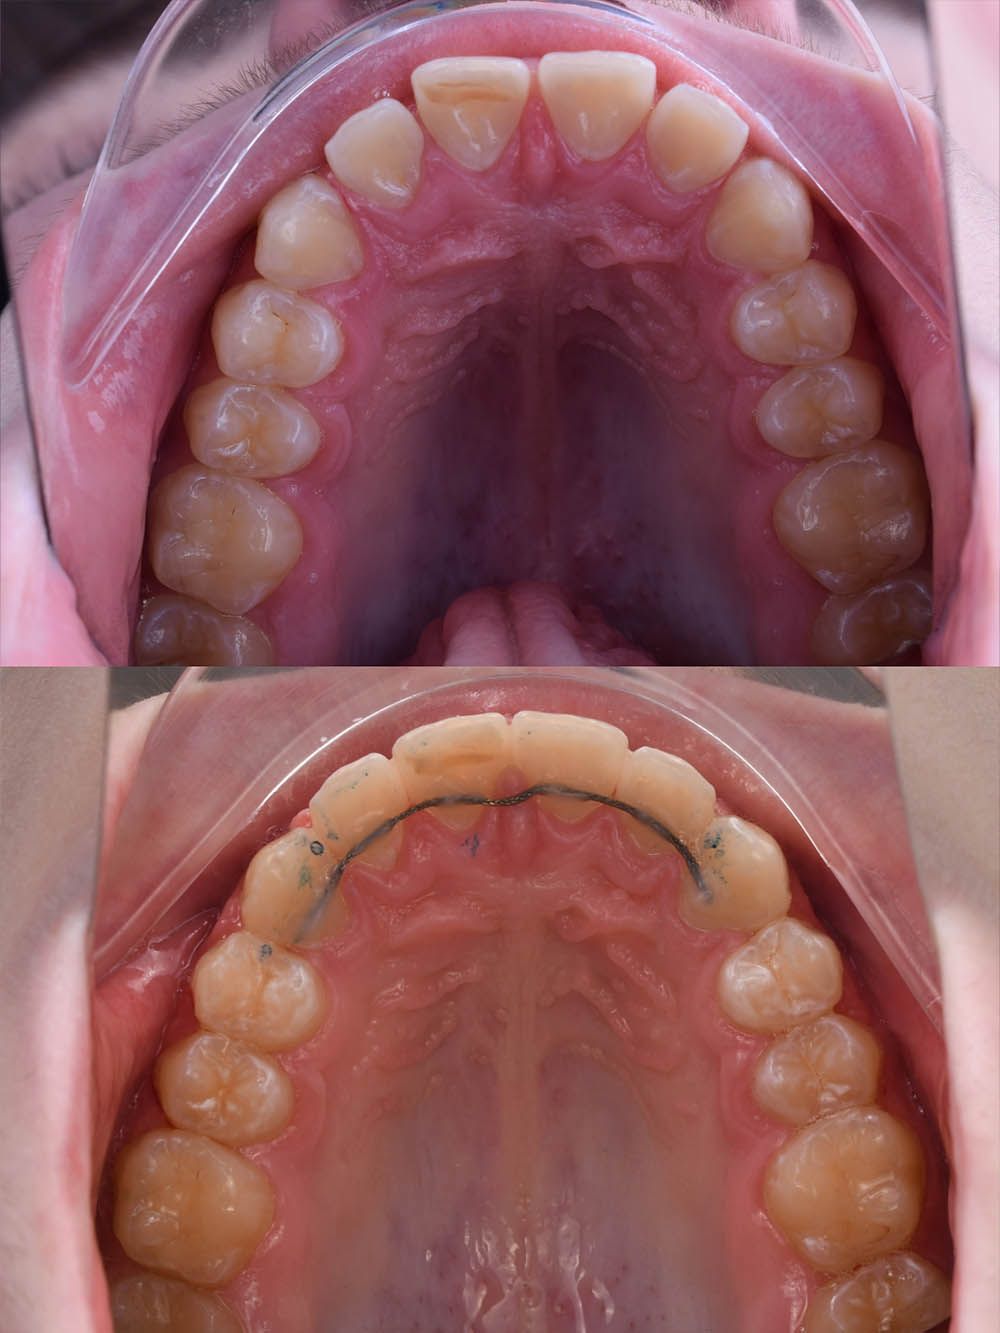

работы специалиста

12 месяцев лечения на брекет-системе

12 месяцев лечения на брекет-системе

12 месяцев лечения на брекет-системе

12 месяцев лечения на брекет-системе

12 месяцев лечения на брекет-системе

12 месяцев лечения на брекет-системе

12 месяцев лечения на брекет-системе

12 месяцев лечения на брекет-системе